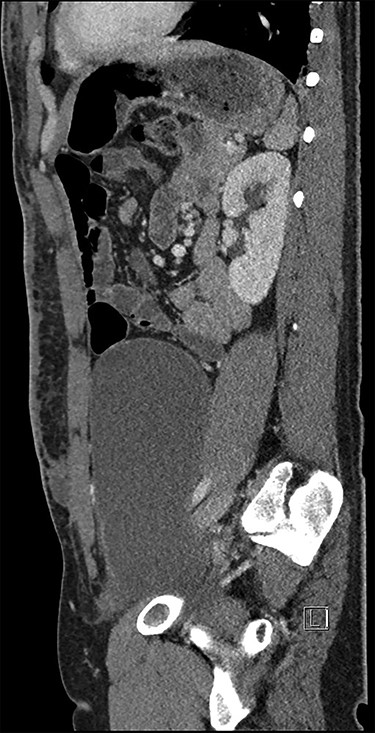

He underwent a computed tomography (CT) abdomen and pelvis, which demonstrated three subcutaneous cystic collections in the left flank, right flank and the left rectus abdominal muscle measuring 12.5 × 3.5 × 10.7, 5.9 × 1.2 × 7 and 1.2 × 1.8 × 2 cm. A large cystic intra-abdominal structure displaced the bladder to the right side and measured 18 × 14 x 7.6 cm (Figs 1 and 2).

The case was discussed at a Gastrointestinal Multidisciplinary meeting and the decision was made for surgical resection of the intra-abdominal lesion via a midline laparotomy. At laparotomy, the cyst was originating from the pelvis and adherent to pubic symphysis, transverse colon and common iliac vein (Fig. 3). The cyst was mostly resected via an en bloc distal transverse colectomy with the cyst leaving right colon and hepatic flexure in situ; however, < 5% was left in place as it was adherent to the common iliac vein and could not be safely resected without risk of significant bleeding.